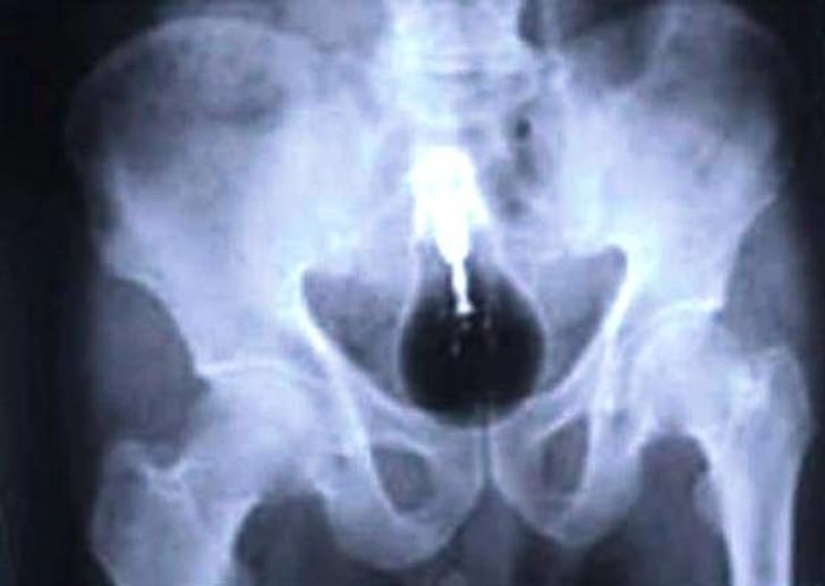

¡Y aquí están las pilas!